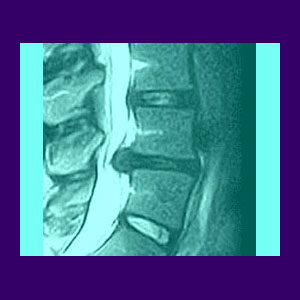

Book an appointment at avid sports medicine in san francisco today! A herniated disc (also called bulged, slipped or ruptured) is a fragment of the disc nucleus that is pushed out of the annulus, into the spinal canal through a tear or rupture in the annulus Discs that become herniated usually are in an early stage of degeneration. The following exercises, in conjunction with proper physical therapy treatment, can help relieve your herniated disc symptoms without surgery.

Diagnosis of Herniated Discs - Back Pain